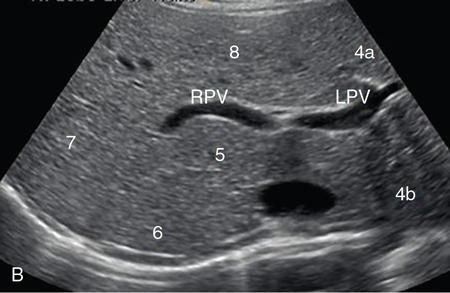

Samarjit Ghuman, Seema Sud, Deeksha Rastogi, Swapnil Sheth, T.B.S. Buxi PLAIN RADIOGRAPHY FOR HEPATOBILIARY IMAGING The diagnostic imaging techniques for hepatobiliary imaging can be intimidating with many techniques/modalities providing the information desired. The job of the diagnostic radiologist includes being familiar with the available choices and pick the ‘best fit’ keeping in mind the pros and cons of each modality, which includes plain X rays, Contrast studies using plain X rays and fluoroscopy, Ultrasound includiojng Doppler and Ultrasound elsastography, CT including multiphase CT and MRI and MRI elastography. Understanding the strengths and weaknesses of every modality as well as the ability to tailor each study individually will help to optimise patient cares. The abdominal radiograph is performed almost exclusively in the supine position and in the AP (anteroposterior) projection. In case of acute abdomen, an erect chest radiograph should also be performed to look for free air under the diaphragm. The standard abdominal radiograph should extend from the diaphragm to the inferior pubic rami, and includes the lateral abdominal wall musculature. Routinely no preparation is required for abdomen radiograph done for hepatobiliary imaging. The radiograph has limited soft-tissue contrast, however, the liver being the largest intra-abdominal organ, casts a perceptible shadow. The margins of the liver can indirectly be seen by outline of adjacent organs like lung, hemidiaphragm, pro-peritoneal fat line, kidney and gas shadows of stomach/colon. The right lobe is seen better than the left lobe of liver. The following pathologies may be visualized on the plain radiograph of the liver. Liver enlargement Liver mass Calcification Increased radiodensity of the liver Decreased radiodensity of the liver An ultrasound is the first line investigation; however, a radiograph may be done for routine evaluation of abdominal pain. The following pathologies may be seen on plain radiograph of the biliary tree. Calculi and Calcifications Gas ULTRASOUND OF HEPATOBILIARY SYSTEM Ultrasonography (USG) is the initial imaging modality of choice for scanning hepatobiliary system. USG is accurate and has high sensitivity and specificity in diagnosing biliary pathologies. Table 9.1.1 shows indications of ultrasound in hepatobiliary system. The real-time nature of ultrasound lends itself to demonstrate mobility of calculi and sludge and the sonographic Murphy sign can easily be elicited during scanning. The main disadvantage is operator dependence, patient’s body habitus, presence of gas which can obscure the visualization of organs, overlying bandages in a postoperative patient and incomplete evaluation in a nonfasting state. USG of upper abdomen should be done after 6–8 hours of overnight fasting. Milk and fatty food should be avoided as they cause contraction of the GB and may cause the GB walls to appear thickened. History of previous surgery, especially cholecystectomy should be elicited. The patient may be positioned in supine or left lateral decubitus position. The GB can be scanned from a high/lateral view, looking through the ribs in supine position or through a sub-costal view in left lateral decubitus position. Position of patient may be changed to demonstrate mobility of structures. The GB is an anechoic structure which is located in the GB fossa along the posterior and inferior aspect of the liver. It has a fundus, body and a neck. It should always be examined in at least two planes (Fig. 9.1.6A and B). The wall of the normal GB should measure 3 mm or less and pathological GB wall thickening can be due to cholecystitis or a neoplastic aetiology. Calculi appear as mobile hyperechoic foci, with distal acoustic shadowing. Other pathologies include polyps and sludge which can be differentiated on the basis of their mobility. The CBD measures less than 6 mm in diameter with increase in the diameter with patient’s age and after cholecystectomy. The CBD is usually scanned in an oblique subcostal plane with the patient in the left decubitus position (Fig. 9.1.7). Dilatation of the intrahepatic biliary radicles is readily assessed with USG and normal intrahepatic biliary radicles are usually not appreciated on USG. Ultrasound of the liver, broadly, is done to assess the size, surface (smooth, coarse or lobulated) parenchymal echogenicity (increased or decreased) vascularity and for presence and evaluation of intrahepatic masses or fluid collections. The liver is divided into right and left lobes by plane of middle hepatic vein which passes through GB fossa and notch of IVC (Cantlie Line). Couinauds classification is the most commonly used system for liver segmental anatomy and described liver into eight functional segments. It is based on distribution of portal and hepatic veins. Every segment has its branch from portal vein, hepatic artery and bile duct (Fig. 9.1.8). Curvilinear transducer (3–5 MHz) is used for routine examination of liver and GB (Fig. 9.1.9). A high-frequency linear transducer (9–11 MHz) (Fig. 9.1.10) can be used to look for subtle irregularity of the liver surface for early Cirrhosis and fine details of GB wall. The liver is scanned in deep inspiration, which causes inferior movement of liver, so that superior borders of the liver are well visualized. Supine position is used for the size of the liver. The measurement is made in sagittal mid clavicular position on right side, in craniocaudal dimension. It is taken from diaphragm to the lower end of the liver. It should be <16 cm and varies with age and sex. The liver is divided into four vertical sectors by three hepatic veins and plane of bifurcation of portal vein divides these 4 sectors in to 8 segments. The right hepatic vein creates vertical plane in the right lobe separating segments V and VIII (anterior) from VI and VII (posterior). The portal vein bifurcation creates a transverse plane and divides these segments into superior (VII, VIII) and inferior segments (V, VI). The left hepatic vein divides the left lobe into medial (IVa, IVb) and lateral sectors (II, III). The left portal vein divides left lobe into superior (Iva, II) and inferior segments (III, IVb). The middle hepatic vein separates medial segments of left lobe (IVa, IVb) from anterior segments of right lobe (V, VIII). Ligamentum teres separates segment III from IVb. Ligamentum venosum separates segment I from IV and II. Cystic duct is an anechoic tubular structure which connects neck of the GB to the extrahepatic biliary tree. In long axis view of GB, the neck of the GB is related to main lobar fissure which appears as a linear echogenic line which runs obliquely between neck of GB and right portal vein. In the right oblique sub coastal view CBD is seen anterior and parallel to portal vein. A series of standardized sections or views may be obtained for liver scanning. Transverse Subcostal View: In this view the probe is angled cephalic and placed transversely under the ribs on the right side and portions both lobes of the liver can be seen (Fig. 9.1.11). Mid Transverse View (Fig. 9.1.12) in this transducer is kept in transverse plane in the midline below the xiphisternum. It visualises the liver in an inferior to superior transverse oblique plane and portions of both lobes of liver can be seen along with right and left portal veins. This view is obtained by angling the transducer superiorly toward the hepatic venous confluence. In this view, we can see the three hepatic veins joining the IVC. Right Parasagittal View for Both Right Lobe and Kidney: This view allows assessment of inferior right lobe of liver. It also allows assessment of relative echogenicity of liver and renal cortex as both are seen together in the same image. Normal liver parenchymal echogenicity is greater than renal cortex and less that renal medulla (Fig. 9.1.14). Parasagittal Right MidClavicular View: In this transducer is kept in sagittal plane in right midclavicular line, and oriented supero-inferiorly. This is the standard view for assessing craniocaudal span of liver (Fig. 9.1.15). Parasagittal View for the Left Lobe: For evaluation of left lobe of liver and lateral segments (2 and 3) (Fig. 9.1.16). This view is obtained along the direction of the main portal vein. CEUS of the liver is done to evaluate Focal Liver Lesions and complements traditional B mode ultrasound and Doppler study. It is a simple, accurate and cost-effective tool complimenting indeterminate CT and MRI findings or for characterization of lesions in patients who cannot receive CT/MRI contrast and can be used in patients with compromised renal function, with minuscule risk of side effects. As CEUS is real-time, microvasculature can be studied along with tissue perfusion kinetics. Indications and uses of CEUS: Contrast agents and technique: Interpretation: Contrast-enhanced ultrasound of a hepatic hemangioma in different phases (Fig. 9.1.19). Limitations of CEUS: Liver elastography is a noninvasive method for diagnosing liver fibrosis. Liver fibrosis is induced by chronic liver disease leading to cirrhosis and liver cancer. Liver biopsy is the gold standard for diagnosing the degree of fibrosis and for staging but it is an invasive method. Elastography helps in analysing the elasticity or the stiffness of the tissue. A stiffer liver tissue indicates fibrosis or chronic liver disease. ARFI is based on the principle of measuring Shear wave velocity. Short duration acoustic pulses which are generated in the tissue and these give rise to shear waves which travel, perpendicular to the ultrasound beam. These shear waves cause tissue displacement followed by recovery. This displacement and recovery depend on tissue stiffness. To monitor these shear waves US beams of low intensity are emitted continuously parallel to the main beam along with the push pulses, and these beams can gather data regarding the tissue stiffness. The shear waves cause tissue displacement and this tissue then recovers from the impulse. From this data the degree of tissue stiffness can be obtained which is displayed either as a map or quantitatively where tissue elasticity is expressed as shear wave velocity measured in meters per second. F0, normal; F1, enlarged fibrotic portal tract; F2, periportal/initial porto-portal septa with intact architecture; F3, architectural distortion with no obvious cirrhosis; F4, cirrhosis. It is also known as Transient Elastography (TE) and works on the similar principle as ARFI, the difference being that B mode ultrasound image is not produced. DOPPLER OF PORTAL VEIN The portal vein divides at the portahepatis into right and left branches. The right portal vein divides into anterior and posterior branches, and the left portal vein divides into medial and lateral branches. Portal vein shows a continuous, forward low-velocity flow (15–28 cm/s) on colour Doppler scanning. The flow is hepatopetal, that is, towards liver and is red in colour as it is flowing towards the transducer. It has an undulating pattern and shows respiratory variation with increase flow in inspiration. It may reflect cardiac variation and shows postprandial increase calibre and flow in healthy individuals. Normal Doppler waveform of portal vein (Fig. 9.1.22). Portal hypertension can be defined as elevated pressure within the portal venous system resulting in impaired blood flow through the liver. INTRAOPERATIVE PANCREATIC AND HEPATIC ULTRASOUND Intraoperative ultrasonography of the pancreas was first described in 1980 by Lane and Glazer. It is an important technique for guidance of both open and laparoscopic surgical procedures of the pancreas. As the transducer is in direct contact with the organ of interest, with no interference with air of adjacent soft tissue, it provides good resolution. It is considered superior to CT and MRI in assessing the intraoperative tumour resectability and vascular invasion and guiding resection. Indications and uses For intraoperative US during open surgical procedures, a high-frequency linear-array transducer or the hockey stick transducer (Fig. 9.1.23) are used which create high-resolution detail of the exposed pancreas. The side-fire curved linear-array transducer is effective for obtaining a wider view of the pancreas and its surrounding structures and for scanning the liver. Intraoperative hepatic ultrasound gives the real-time visualization of the hepatic anatomy and aid for surgical planning and making decision during surgery. Indications and uses Transducer and technique Limitations MULTIDETECTOR CT OF THE HEPATOBILIARY SYSTEM AND CHOLANGIOGRAPHY The cross-sectional plane of the patient is denoted as the x/y plane. The plane along which the table moves is the ‘z’ plane. Multidetector CT denotes more than one detector along the Z-axis, with the latest machines having up to 320 and now even 640 rows of detectors. This provides CT with very fast, high resolution, isotropic images which can be reconstructed in any plane or even curved planes. MDCT scanners can comfortably scan the entire abdomen in 10 seconds or less, thereby allowing visualization of different phases of contrast enhancement. Contrast Media (CM) after administration gets distributed from the intravascular compartment into the interstitial spaces. Intravascular arterial enhancement (for angiography) and parenchymal enhancement have different kinetics. Parenchymal enhancement is directly proportional to total iodine dose being administered and inversely proportional to weight, which is a marker of extracellular volume into which contrast redistributes. Rate of iodine administration has no effect on degree of parenchymal enhancement. As a general rule approx. 500–600 mg of iodine/kg body weight achieves adequate hepatic parenchymal enhancement. For a 60 kg adult, this translates into approx. 100–120 mL of contrast containing 300 mg of iodine per mL. Intravascular or arterial enhancement is controlled by rate at which iodine is administered (flow rate and iodine concentration of CM) iodine flux and duration for which contrast is administered longer injection also leads to better overall arterial opacification due to recirculation effects. This principle is made use of while performing abdominal CT Angiography. Higher iodine delivery rate per unit time using a higher iodine concentration contrast medium also improves conspicuity of vessels and hypervascular lesions such as HCC. For identical parameters, difference in arterial enhancement between patients is dependent on cardiac output with enhancement being inversely proportional to cardiac output. For optimal imaging and enhancement, in multiphase imaging and angiographic studies, contrast material administration and parenchymal or vascular enhancement must be synchronized with CT data acquisition. The two main methods are: Test bolus technique: A test dose of contrast is given and the time to peak enhancement is measured in a ROI placed in a target vessel this information can be used to tailor CT acquisition. Automated bolus Triggering: ROI is placed in target vessel (usually aorta at level of diaphragm) on a plain image. While CM is injected, a series of low dose scans is obtained through the ROI. When the density of contrast reaches a predefined threshold (e.g. 150 HU), at time ‘t’ the scan is automatically triggered. The trigger delay after time ‘t’ is a minimum of 2 sec, and can be programmed to any value. Bolus tracking is nowadays the method of choice for planning contrast medium administration and this technique provides more homogenous opacification. Saline chase is recommended in all multiphase protocols. Significant amount of contrast may be present in the peripheral veins after injection of IV contrast and use of saline chaser leads to better vascular enhancement and lower overall contrast dose (Fig. 9.1.24). Using the above, a standard sequence of acquisitions and contrast enhancement techniques can be tailored to the pathology and organ of interest and pre-programmed into the scanner menu, which includes kVp, mAs, pitch, rotation time, slice thickness etc. This is known as a scan protocol. However, these can be modified as necessary. For example, rotation time can be shortened and pitch can be increased for breathless patients to reduce scan times (Table 9.1.4). Multidetector CT is the workhorse of hepatobiliary imaging. It plays a major role in imaging congenital, traumatic, infective, neoplastic and vascular pathologies of the hepatobiliary system. Scans can be obtained with or without intravenous (IV) iodinated contrast material administration. Multidetector CT scanners are capable of imaging multiple phases at different points of time following injection of contrast and provide dynamic imaging due to fast scan times and rapid coverage of the abdomen. Indications for liver imaging include, but are not limited to: Unenhanced Scan: Hepatic fat estimation, radio opaque biliary calculi. Single Phase Scans: Liver abscess, polytrauma, follow up of known oncologic or benign lesions, abdominal pain, suspected cholecystitis. Multiphase Studies: Evaluation of hepatic masses, imaging in cirrhosis, imaging for resectability, liver donor evaluation, malignancy of GB, hepatic venous outflow obstruction etc. CT Angiography of Hepatic Vessels: Trauma, vasculitis, post-operative bleeding and as a part of multiphase studies. Depending on the indication, scanning protocols can be tailored to highlight the suspected pathology and provide relevant answers for further management (Table 9.1.5). The liver has a dual blood supply, most of which is derived from the portal vein. After injection of contrast, until the portal vein provides recirculated contrast material filled blood to enhance the hepatic parenchyma, the hepatic parenchymal enhancement is relatively poor and dependent only on the hepatic artery. The hepatic arterial phase can be divided into an early arterial phase without any portal opacification, a late arterial or portal inflow phase in which there is some portal vein opacification. This is followed by a portal venous phase in which portal and hepatic veins are enhanced (also called the hepatic venous phase in some articles). In addition, an unenhanced/plain scan and an equilibrium phase can also be acquired. Tumour conspicuity of hypervascular lesions was found to be best on the late arterial or portal inflow phase (Fig. 9.1.25). The early arterial phase is seen up to 10 seconds after trigger, and provides ‘angiographic’ images of hepatic arterial anatomy. This phase is used to provide details regarding arterial anatomy and morphology. Later arterial phase 18–23 seconds, portal venous phase 60–70 seconds and equilibrium phase 180 seconds are obtained after trigger. Equilibrium phase images have been shown to increase detection of hepatocellular carcinoma in cirrhotic patients. The portal venous phase is the standard phase for routine chest/abdomen survey and follow up of hepatic abscesses and hypovascular metastases. Single Phase Scan Protocol: Oncologic follow-up, Liver Abscess – For routine single-phase CT, contrast as per body weight can be injected over 40 seconds and scanning can be done after an empiric delay of 70 seconds from the beginning of injection. This protocol provides good parenchymal enhancement and portal and hepatic vein visualization. Plain scan is optional. Dual-Phase Scan Protocol: Hepatic evaluation in patients with malignancies known to have hypervascular metastases – Neuroendocrine tumours, renal cell carcinoma, thyroid carcinoma, (.) melanoma etc. Late arterial Phase 20–22 seconds and Portal venous phase at 60–70. Plain scan optional. Hepatic Resection Protocol: For patients with known hepatic mass being evaluated for resection. Early arterial phase provides pure arterial or angiographic images. It is obtained at 8–10 seconds post trigger followed by portal venous phase at 60–70 seconds. This is required for arterial and venous anatomy and volumetric evaluation if required. Plain scan is not required. In case a hepatic mass needs characterization as well as resectability planning, late arterial and equilibrium scans may also be done. Indications for angiography are further discussed in the section on angiography. The same biphasic protocol using angiography or arterial phase images is used in patients with trauma suspected to have pseudoaneurysms, hepatic artery thrombosis or dissection in transplant recipients, evaluation of living donors and in patients in whom an angiographic ‘road map’ is required prior to intervention. Triphasic or 4 phase scan Protocol: Standard of care for patients with cirrhosis being evaluated for Hepatocellular carcinoma and for patients being evaluated for hepatic mass of uncertain aetiology. Late arterial phase scan: 20–22 seconds, Portal venous scan at 60–70 seconds and Equilibrium scan at 180 seconds. Plains scans are optional. Our institutional practice is to always do plain scans in patients who have undergone hepatic intervention. Plain scans also help to visualize siderotic and steatotic nodules. A further delayed scan is suggested by some authors at 10–15 minutes for characterization of hepatic masses of uncertain provenance. This is particularly useful in cholangiocarcinoma (Table 9.1.6).

Hepatic anatomy on ultrasound